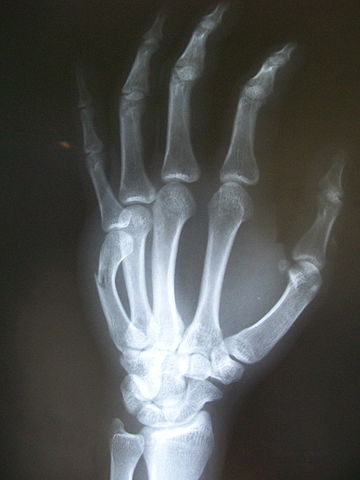

What are the key components of a hand fracture ?

Fractures are simply break in the bones. This happens in most cases due to injury, but the injury is never in isolation to the bones only. There is injury to soft tissues, ligaments, and in open fractures – break in the overlying skin as well. All these factors drastically effect the best way to treat the underlying fracture whilst restoring the hand function.

What does a hand fracture surgery involve?

The objective of hand fracture surgery is to achieve fixation of the broken bone segments with as minimum manipulation or dissection as possible. This is most instances can be achieved with K wires which are simply stainless steel nails drilled through the skin across the fracture site. This modality is widely practiced , remains least invasive and can be modified as per most fracture configurations